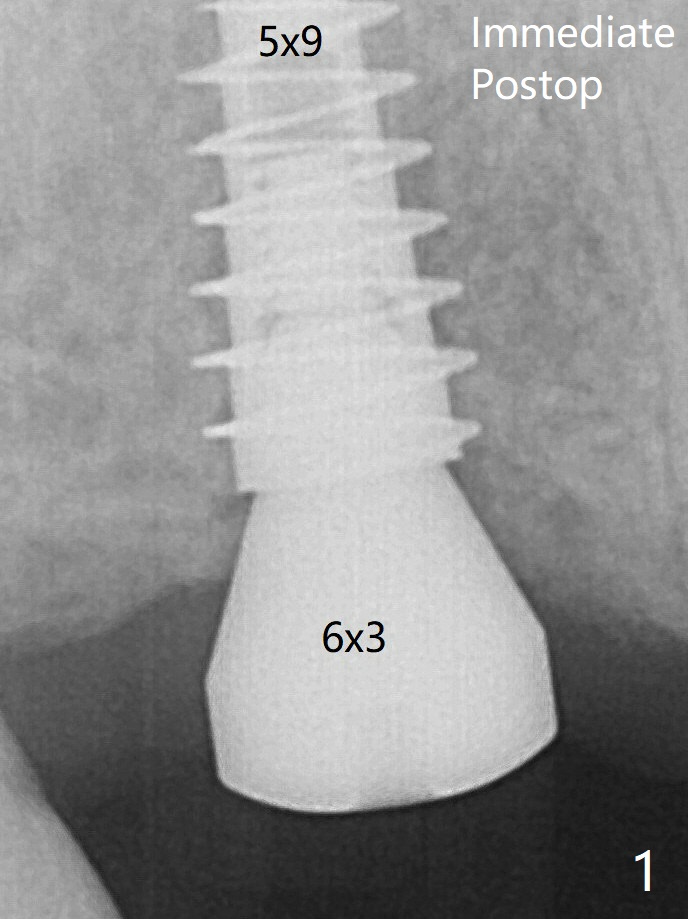

术后5.5个月放置修复基台(图二),基台直径再小一号,放置就可能容易些,容易就位。